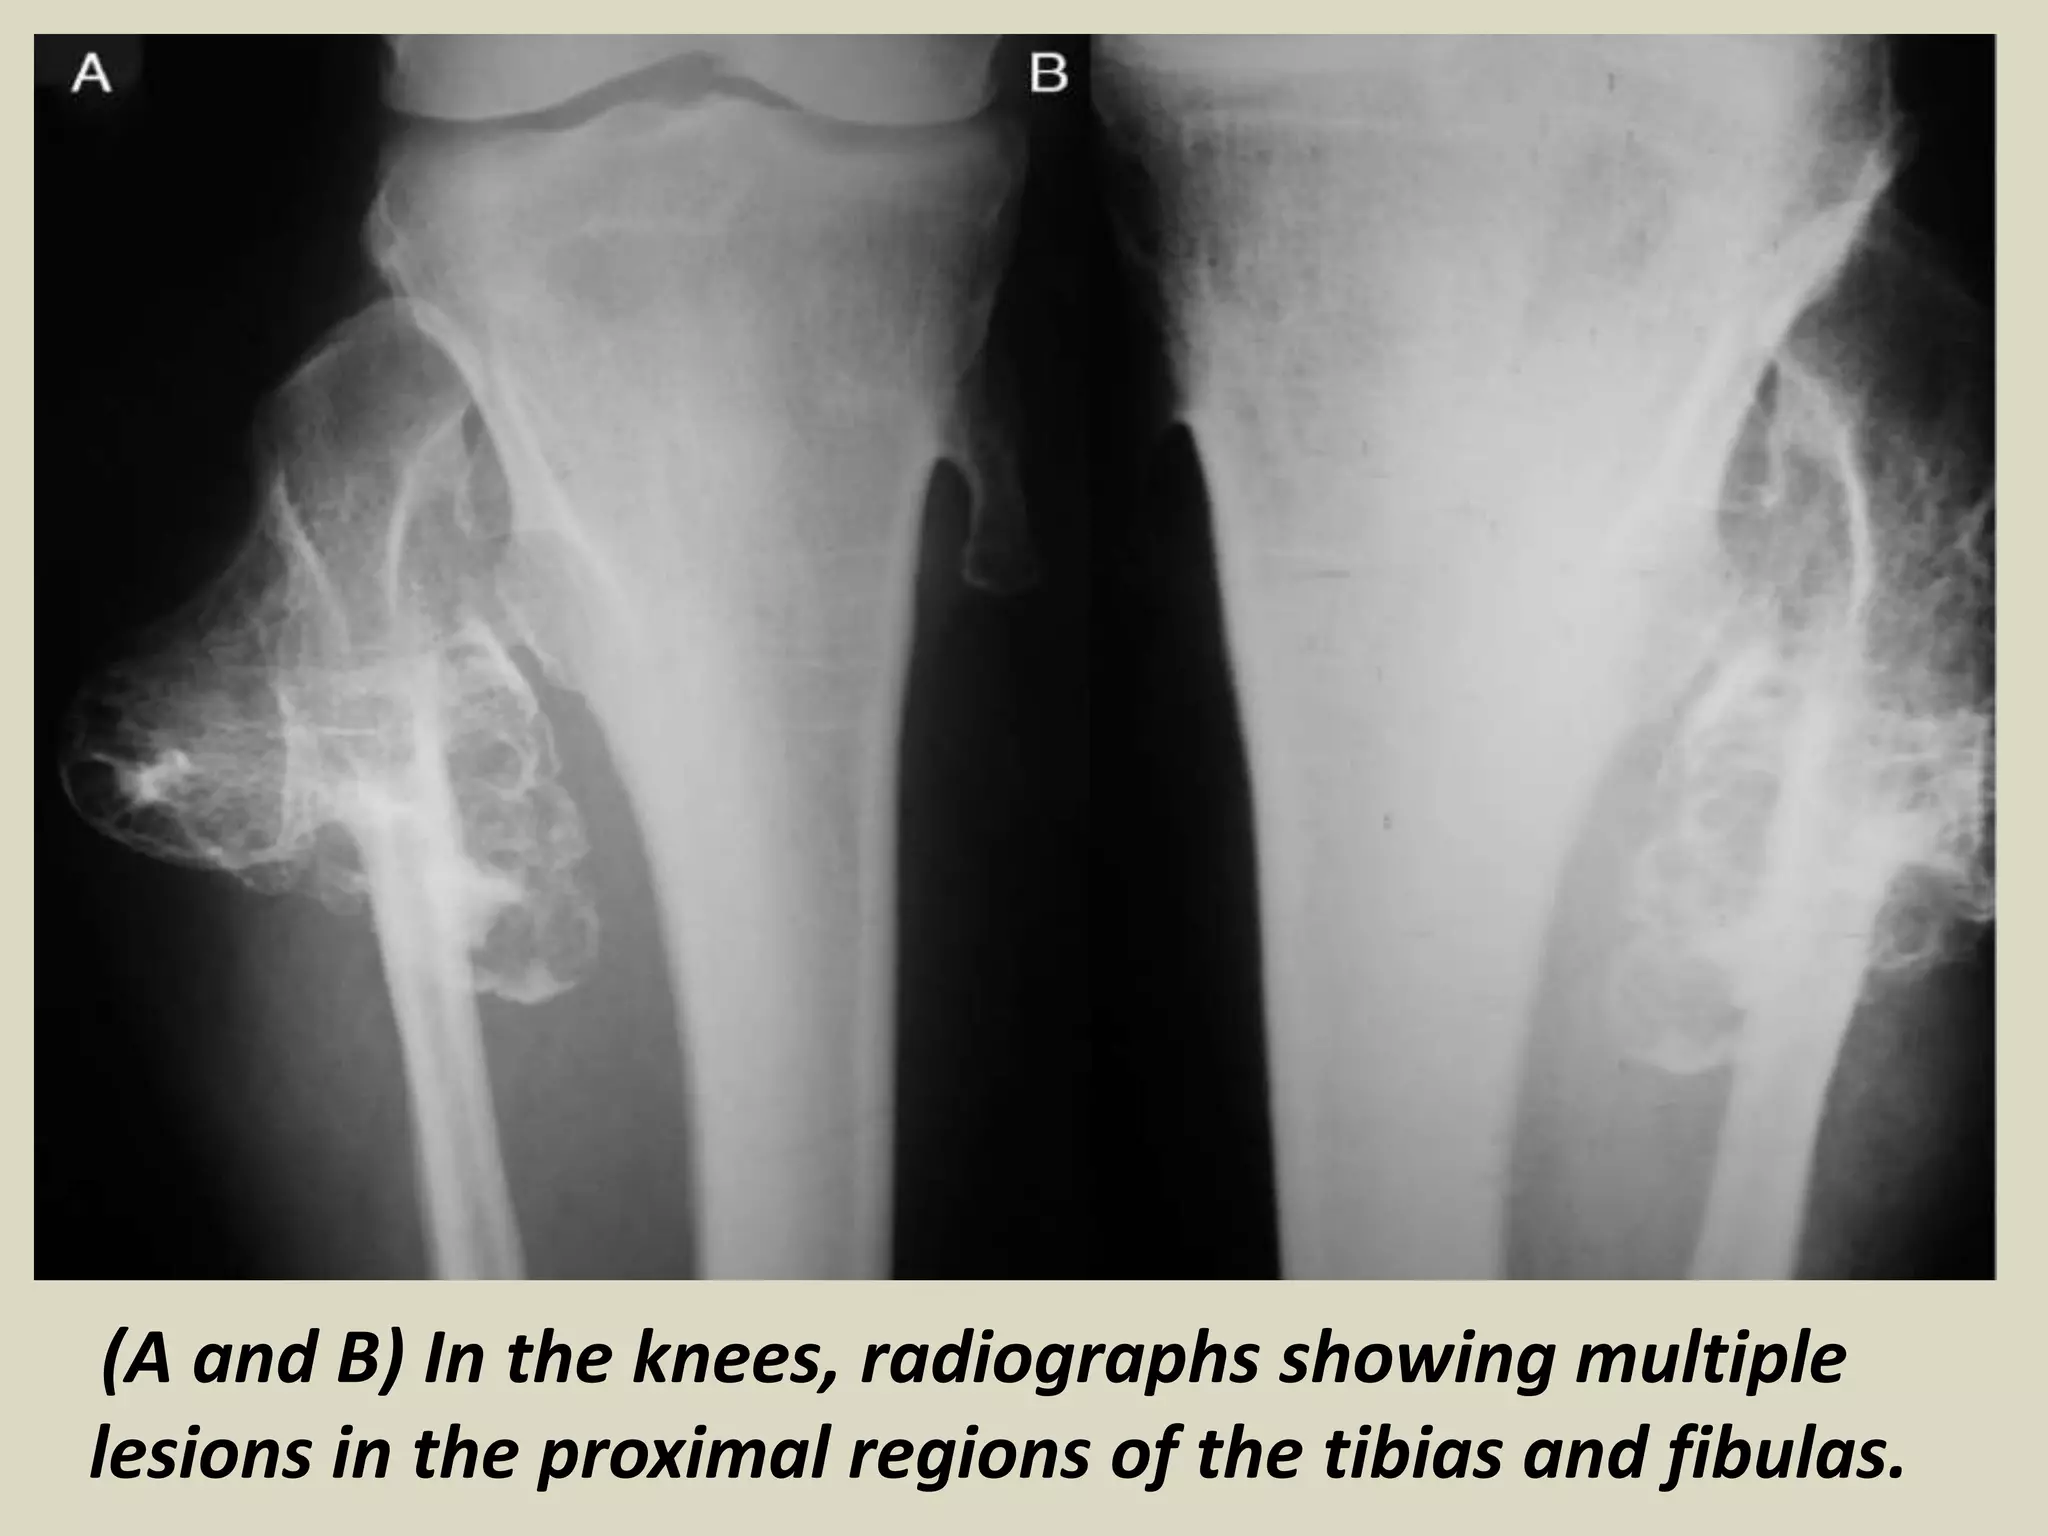

OSTEOCHONDROMA (EXOSTOSIS)

(A and B) In the knees, radiographs showing multiple

lesions in the proximal regions of the tibias and fibulas.